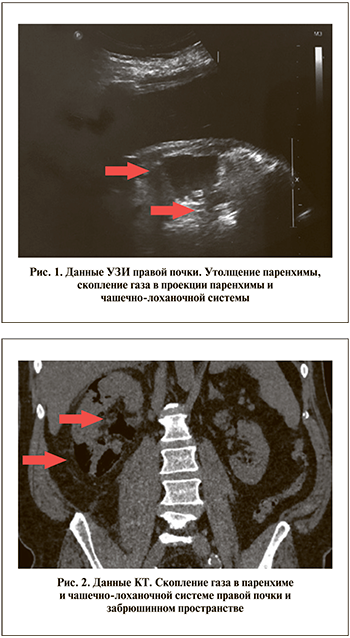

По данным УЗИ, отмечено увеличение размеров правой почки, ее подвижность резко ограничена, контуры нечеткие, в области верхнего и нижнего полюсов скопление газа (рис. 1). При выполнении нативной КТ газ выявлен в лоханке, чашечках, паренхиме, субкапсулярно, паранефрально с распространением за пределы фасции Героты в забрюшинное пространство (рис. 2). В средней трети правого мочеточника определялся камень размером 6 мм, плотностью 1000 HU. Полостная системы почки не расширена.

Установлен диагноз: мочекаменная болезнь, камень средней трети правого мочеточника. Острый эмфизематозный пиелонефрит справа (3Б по классификации J. J. Huang и C. C. Tseng). Острое почечное повреждение. Сахарный диабет.